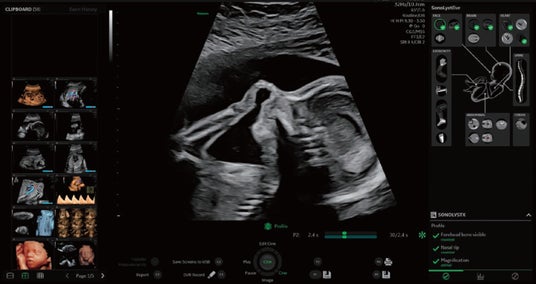

SonoLystは、ワークフロー改善のためにAI手法を用いて開発されたソフトウェアです。ISUOG(国際産婦人科超音波学会)ガイドラインに準拠し、解剖学的な特徴からスキャン中の描出断面が基準断面にどれほど近づいているかを知らせて医師のスキャンをサポートします。フリーズ後は、ガイドラインの基準断面に即したどの部位であるかを自動認識し、ユーザーに提案し、ユーザーがそれを受け入れると、チェック済項目として保存されます。これにより、胎児スクリーニング検査の効率化と検査クオリティの担保、ユーザーの自己学習の推進に貢献します。

SonoLystを用いた検査画面